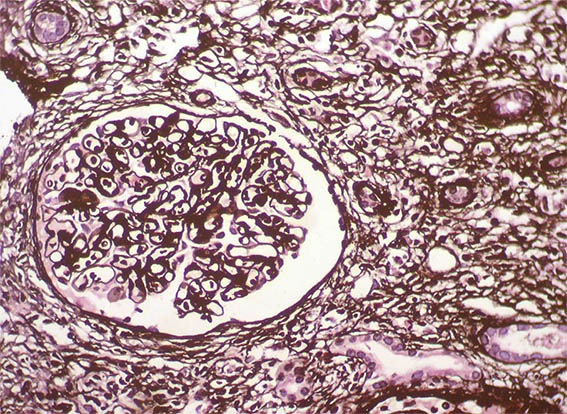

Figure 7. Methenamine-silver stain, X100.

Figure 8. Methenamine-silver stain, X400. Glomeruli with normal characteristics.